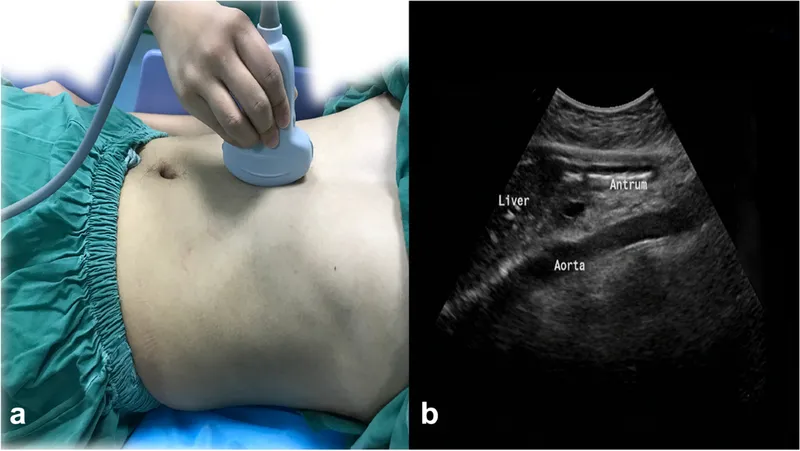

- Probe: Curvilinear (low frequency, 2-5 MHz) or phased array.

- Sagittal midline view in epigastrium.

- Identify antrum: between aorta (posterior) & left liver lobe (anterior).